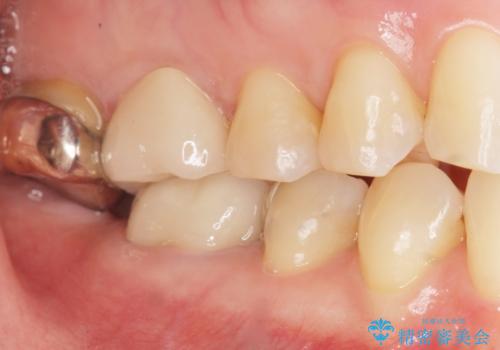

治療後はしみなくなり、違和感のない自然な咬み心地にご満足頂けました。

「割れる心配のないゴールドにしたいけれど、目立ってしまうかしら...」と心配されており、不要に歯質を削合しないよう注意を払い最小限の大きさのインレーを装着したところ、「あまり目立たなくて良かった!」とおっしゃって下さいました。

硬さが天然歯に近いため周囲の歯への影響も少なく、さらに適合もよいため虫歯の再発リスクも軽減できます。

金属なので強度が高く、咬合力の強い方や力が強くかかる部位に適しています。

審美面でセラミックに劣りますが、奥歯の治療には最適な材料です。